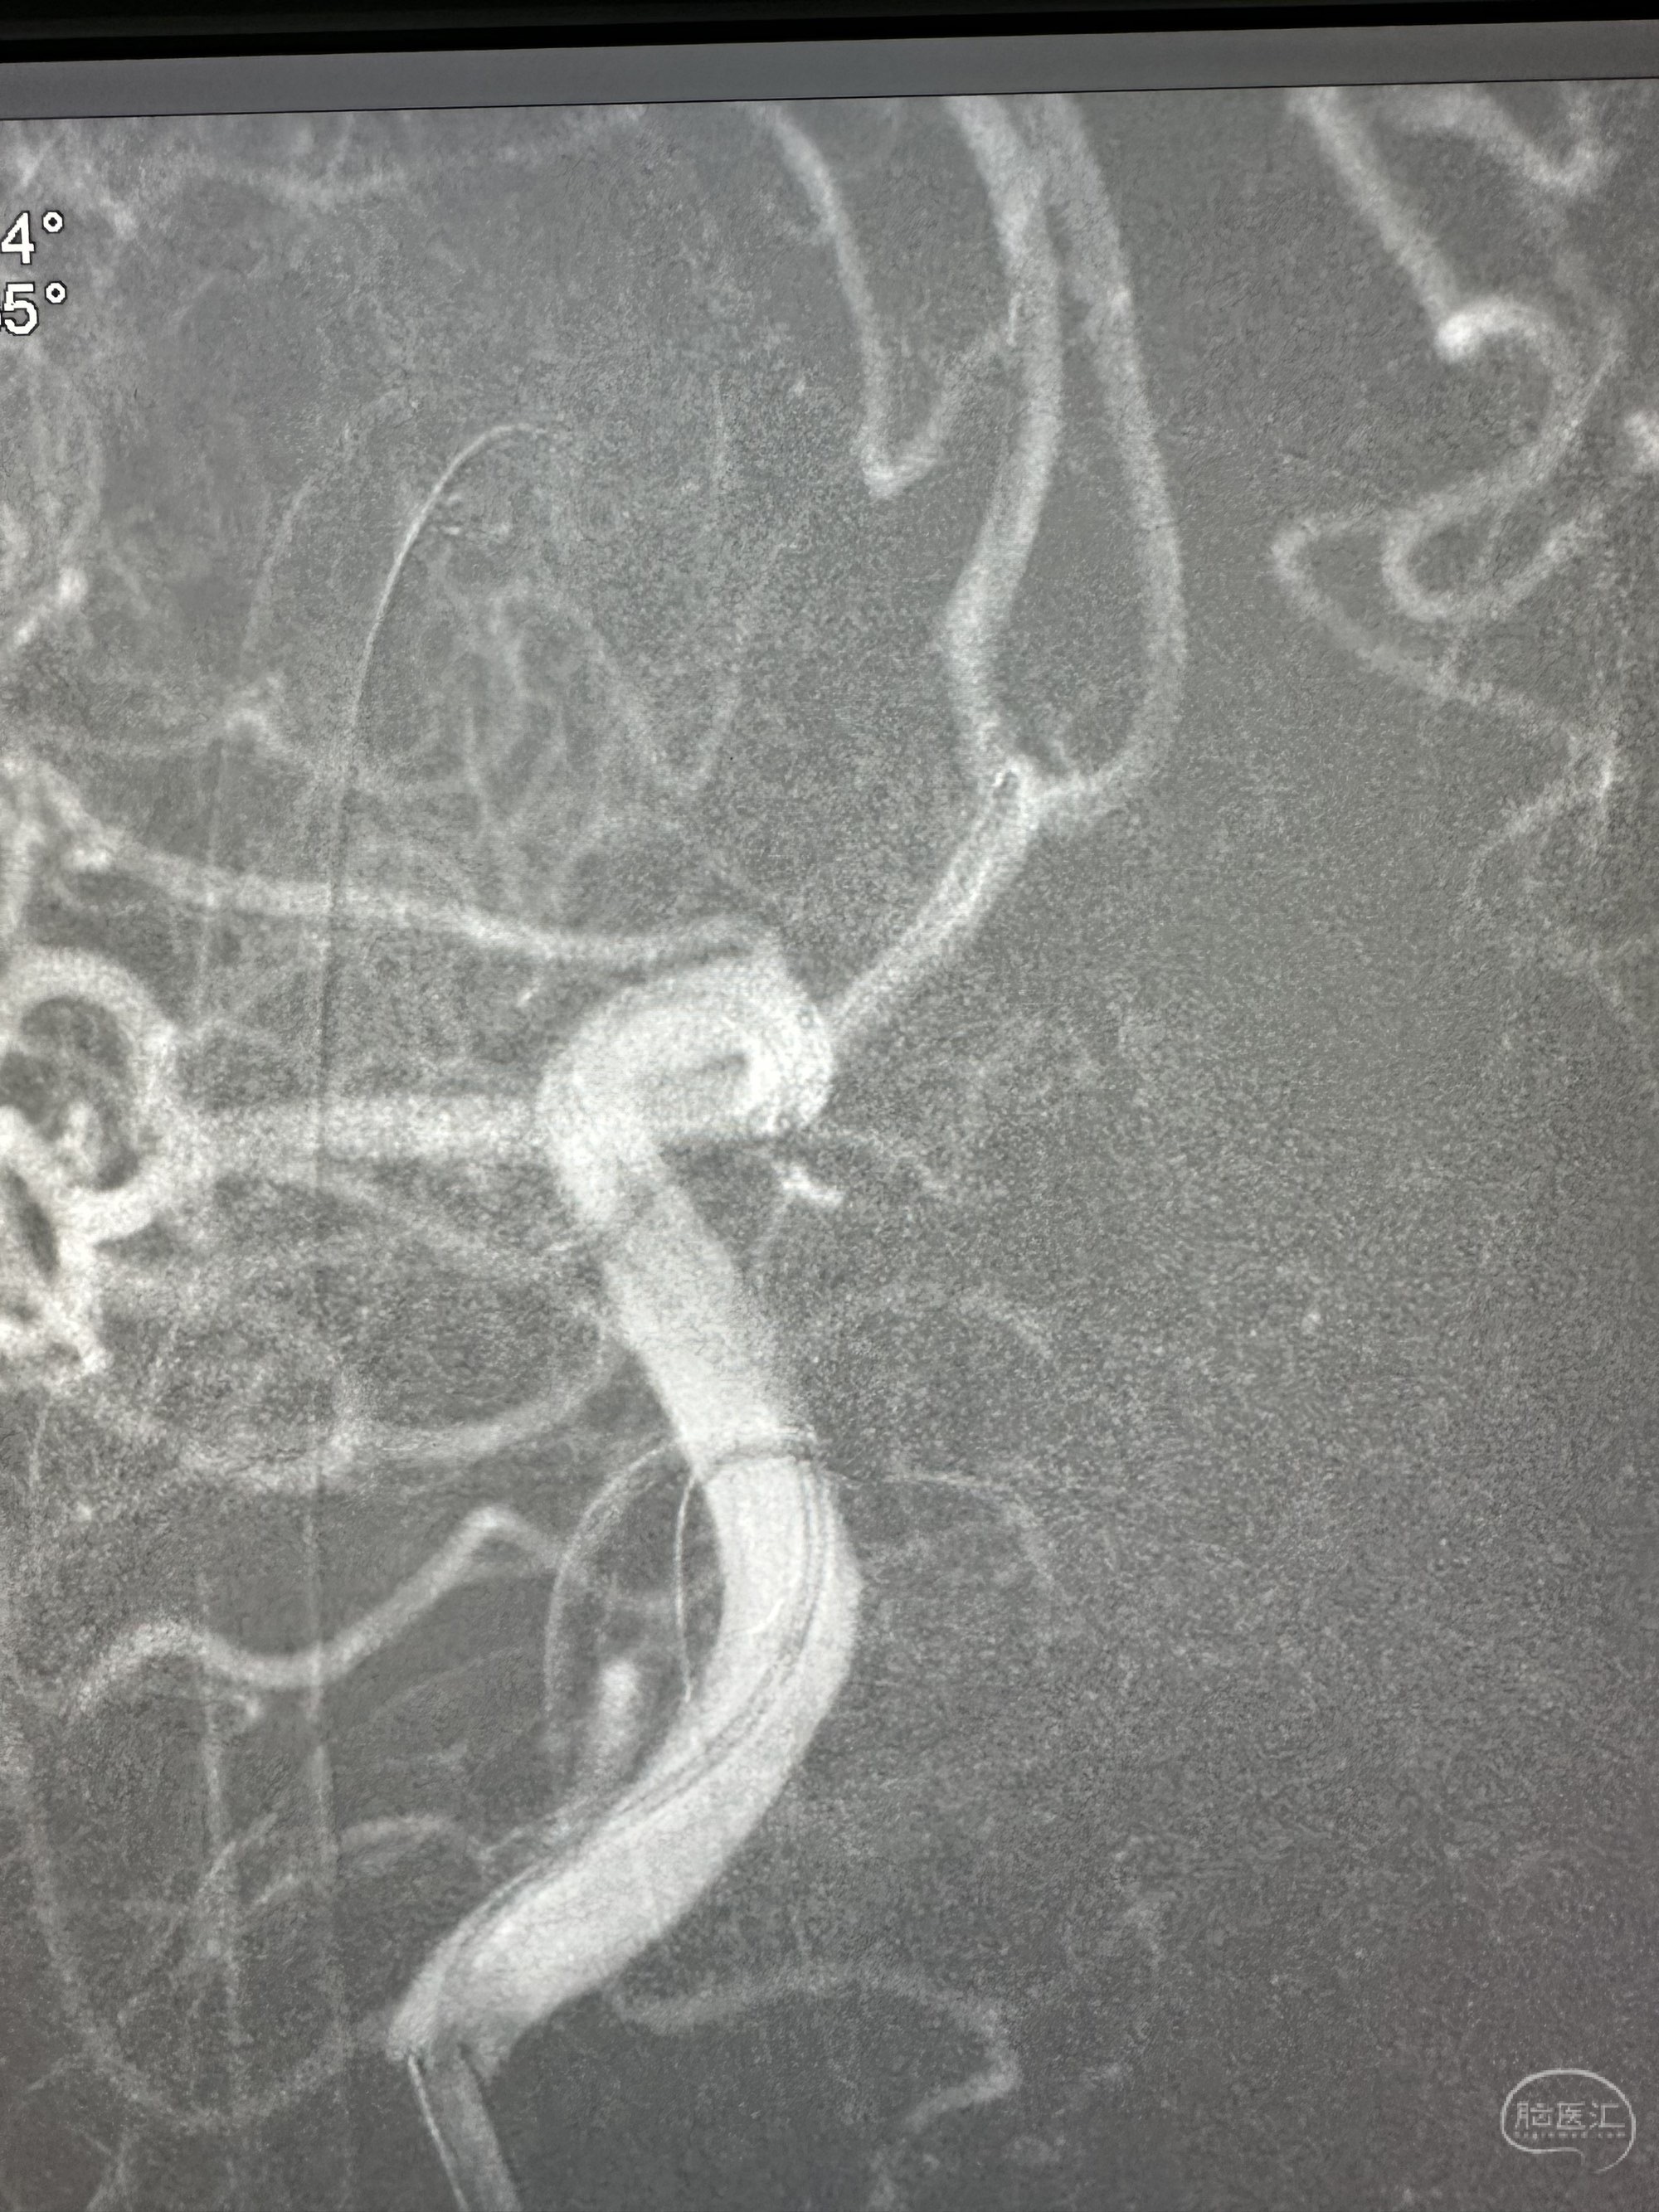

第一枚圈填塞后,换了一个角度造影发现有点出血

补了一个圈,同时释放EP 2支架4*21的支架

再次造影未见出血,准备撤出微导管的时候,一个圈跑出来了,但是还是稳得住

果断再次补了一个圈